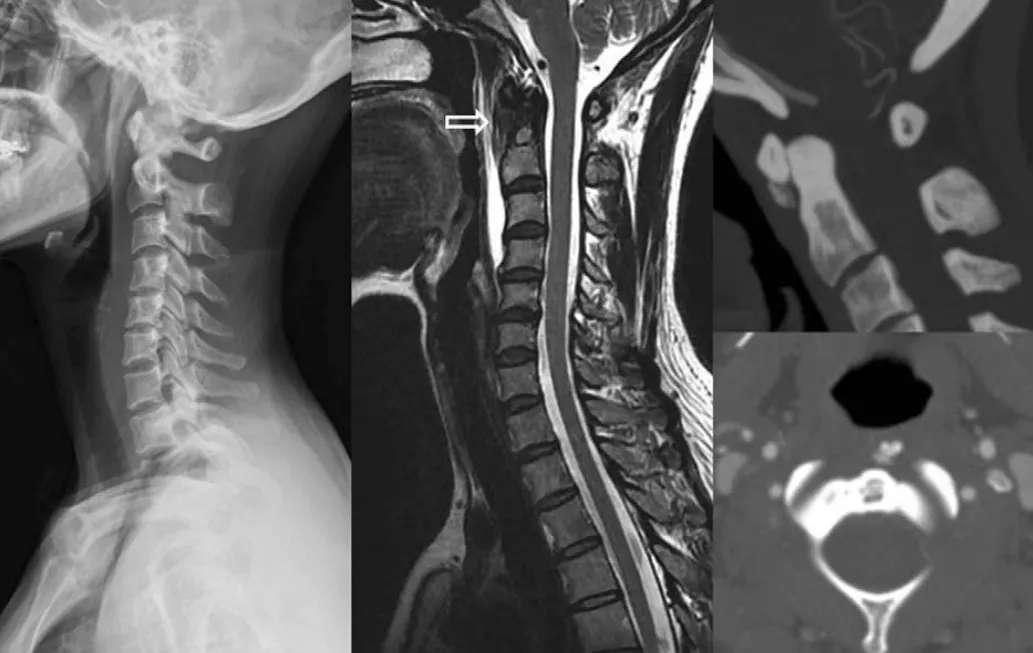

椎前软组织肿胀

颈椎侧位片能够显示上颈椎前纵韧带和颈长肌组成的软组织影增宽,密度增高,正常时宽度为3-4mm,急性炎性水肿时可增宽到1cm以上,并可显示椎前软组织内的钙化影,一般位于C1-2水平。此外,还可见颈肌痉挛引起的颈椎前凸消失。颈椎侧位平片所见的发育性寰椎前弓的下方附属小骨片、寰椎前弓的撕脱骨折以及茎突舌骨肌韧带的钙化极易与本病所见的钙化混淆。

CT的高分辨率能够明确肌腱内的钙化,能够明确是钙化而不是其他骨骼来源的高密度影。钙化一般位于寰椎前弓的下方和枢椎齿状突的前方,少部分可位于下颈椎前侧。CT有助于明确椎体前积液的存在和排除其他病理表现,如骨折或脓肿。MRI对诊断不是必须,但有时可帮助确定软组织异常,排除咽后脓肿,脊椎炎或肿瘤。MRI检查T2加权在椎前可见局限性的裂隙样区域,大多位于C1-4水平,呈高信号改变,这反应是由于炎症引起的积液。T2加权、脂肪抑制序列和T1加权对鉴别积液和脂肪组织、含脂肪的骨髓以及咽后感染、脊椎炎有重要作用。MRI检查在钙化检查方面存在不足,T2加权呈低信号。